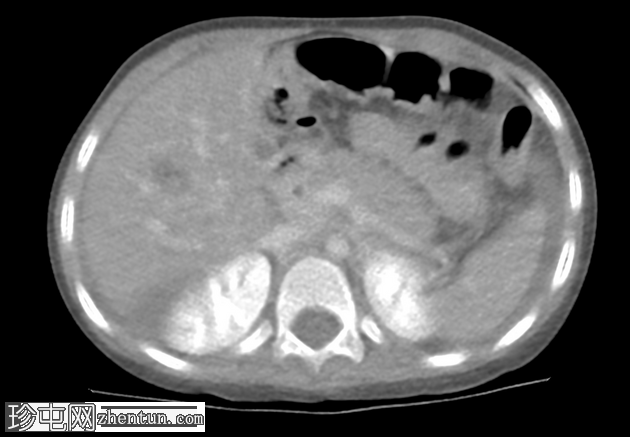

轴向C+延迟期

AAST IV级肝撕裂伤,伴有大面积不规则肝损伤,累及V段(轴向、冠状、矢状)。

撕裂伤区域内未见活动性造影剂外渗。

可见中等量腹腔积血。